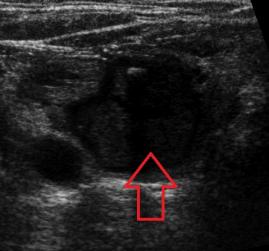

- Tiroid iltihabı (Hashimoto)

- Hashimato'da lazer tedavisi: İlaç dozlarının azaltılması veya kesilmesi ve kilo kontrolü !!!

- Hashimoto hastalığında destek tedavileri